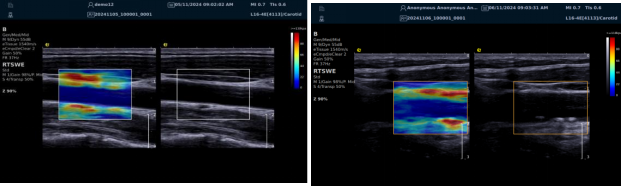

(一)RTSWE 实时剪切波弹性成像技术

RTSWE 技术源于对剪切波的创新研究,通过 MultiPush?超声触诊技术产生振动生成剪切波,OmniSound?平台提升帧频捕获信息并测量杨氏模量。其优势突出:

image.png

? 可视化,对颈动脉内膜和斑块实时弹性成像,彩色编码显示硬度,便于医生区分斑块类型。

? 定量测量方面,分析结果以kPam/s为单位测量颈动脉相关部位杨氏模量,毫米级分辨率显示微小病变,提供 20 余种参数综合评估斑块稳定性和血管硬化因测量取样范围可极度小甚至对于颈动脉内中膜硬度可定量测量,引发不同视角评价极早期动脉硬化评估,实属科研利器。

? 采用马赫圆锥脉冲激励技术,无需按压,减少检查者影响,帧频高、操作简便、耗时短。

RTSWE 是全球唯一的实时全幅全定量剪切波弹性成像系统,OmniSound?平台采集与显示帧频国际领先,对颈动脉结构定量分析和脑卒中早期预防意义重大。